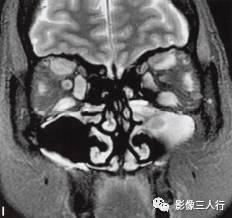

A~C.抑脂T2WI横断面;D~F.T1WI横断面;G~H.T1WI冠状面;I.抑脂T2WI冠状面

横断面显示双侧眼球明显突出,双侧眼球角膜至双侧颧突连线的垂直距离分别为:右侧2.2cm、左侧2.3cm。双侧眼外肌明显增粗,以双侧内、外、上、下直肌明显,短径均可达7mm,且以肌腹增粗明显呈梭形,T1WI等信号(图D~F,图G~H),抑脂T2WI呈明显高信号(图A~C,图I)。双侧眼眶内及球后脂肪增多,双侧眼球内侧至眼眶内侧壁的脂肪厚度增宽。双侧视神经形态及走行正常,双侧眼球晶体、玻璃体形态及信号正常。

影像学检查可帮助该病的诊断与鉴别诊断。CT表现为眼外肌增粗,主要为肌腹增粗,附着于眼球壁上的肌腱不增粗,少数也可同时累及眼外肌肌腹和肌腱。最常累及下直肌,其次为内直肌、上直肌和上提肌,偶尔累及外直肌。MRI表现为受累的眼外肌T1WI低信号,T2WI高信号,压脂T2WI为高信号;晚期眼外肌已纤维化,在T1WI和T2WI均呈低信号。增强扫描急性期时增粗的眼外肌有轻至中度强化,晚期眼外肌纤维化时则无强化。眶内脂肪体积增多表现为球周脂肪尤其是眶前部脂肪的增多。本例影像征象较典型。